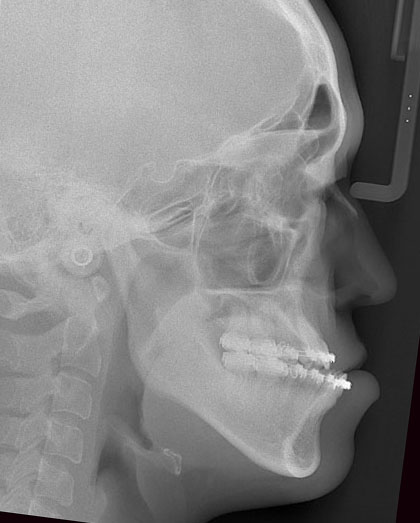

セファログラムを用いた診断

標準的な顔のバランスと比較すると、上顎はやや後方にあり、下顎は大きく前に出ていることがわかりました。そこで、上顎を少し前に出し、下顎を後ろに下げるとともに、上下の顎を一体として回転させることで、顎先の突出感を改善する計画としました。上顎は2.5 mm前方に移動し、後方を4 mm持ち上げる形で回転させる予定としました。